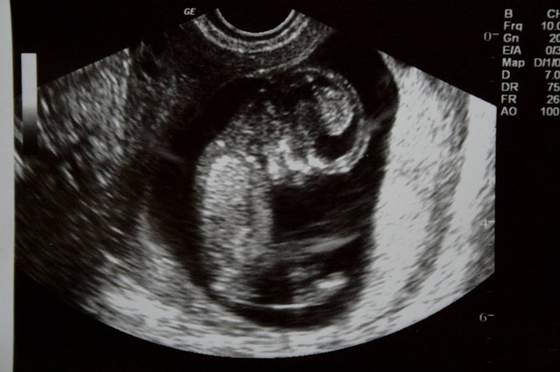

Z maleństwem wszystko ok, rośnie (ma już prawie 6cm, a na ostatnim usg 29 maja miało 164mm), wierzga jak szalone, widać super już rączki, nóżki,narządy w środku i w czasie badanie łapało za pępowinę :-)

FasolinkaZobacz załącznik 630536Zobacz załącznik 630538